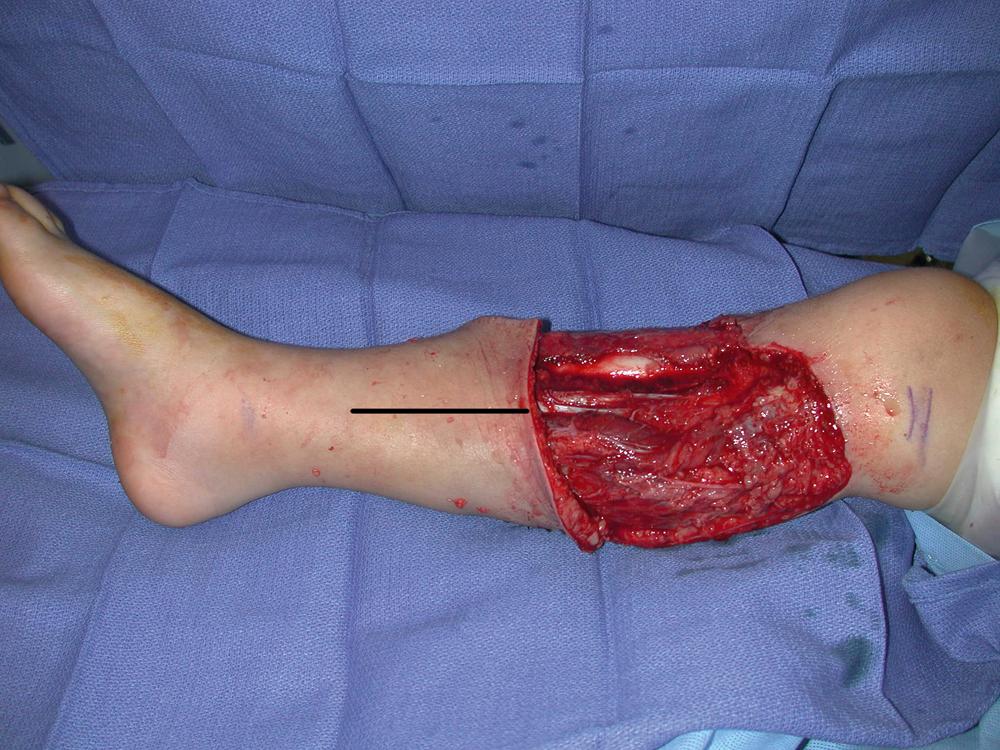

Under general anesthesia with the patient in the supine position, the right proximal tibial wound was debrided and unhealthy looking and traumatized skin was excised. All colonized tissues were sharply removed. The open wound appeared to be fresh and clean after a definitive debridement performed by the plastic surgery service ( Fig. 43.2 ).

Fig. 43.2, An intraoperative view showing a fresh and clean proximal tibial wound after definitive debridement by the plastic surgery service.